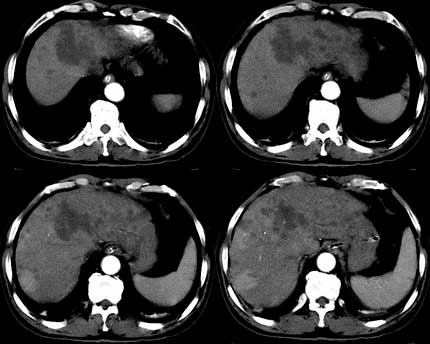

患者 男性 65岁,2005年8月行胆管癌切除术(切除胰头 胆囊及十二指肠),今行ct复查,请会诊,有没有复发?(近期患者发烧,重度黄疸)

是单纯复发还是复发伴肝内转移?我个人认为应当再考虑一下,并倾向于后者。肝总管下端内、后侧见不规则软组织块影,部分侵入肝总管内。其边缘凸凹不平且模糊不清,渐进性不均匀强化。肝总管于此处管径突然变小,其上肝总管显著扩张,内见较均匀液性密度,管壁也很光整。肝内多发低密度病灶用复发引起的肝内胆管扩张显然不能解释的通,病灶分布与胆内胆管的走行不一致。而且随着时间的延续病变更加清晰,没有强化,部分还可见牛眼征。

考虑胆囊癌术后复发及肝转移,肝门区胆管扩张明显,左肾囊肿。